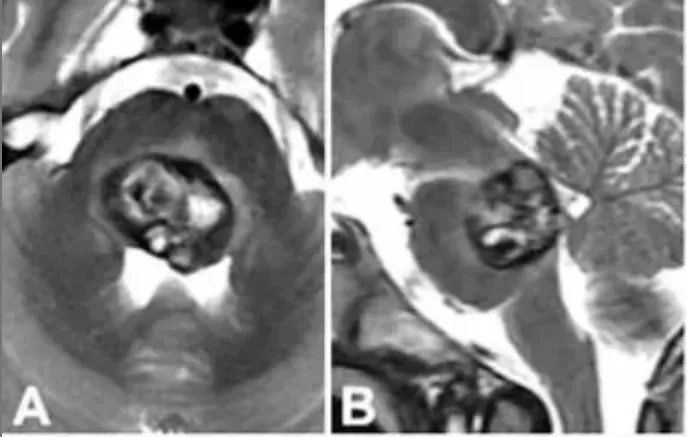

脑干手术成功率多大? 偏瘫、走路不稳、脸歪口斜,我从没想过我的脑干海绵状血管瘤会让我情况如此严重。当医生指着我的影像告诉我,我的血管畸形已经长得非常大时。看着那个感觉都要...